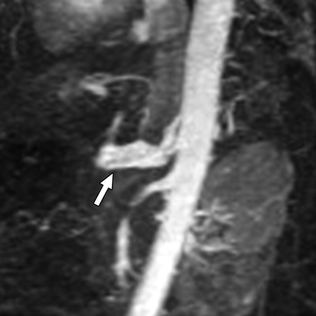

Vascular EDS Photo Gallery

Pictures of vascular EDS and its symptoms